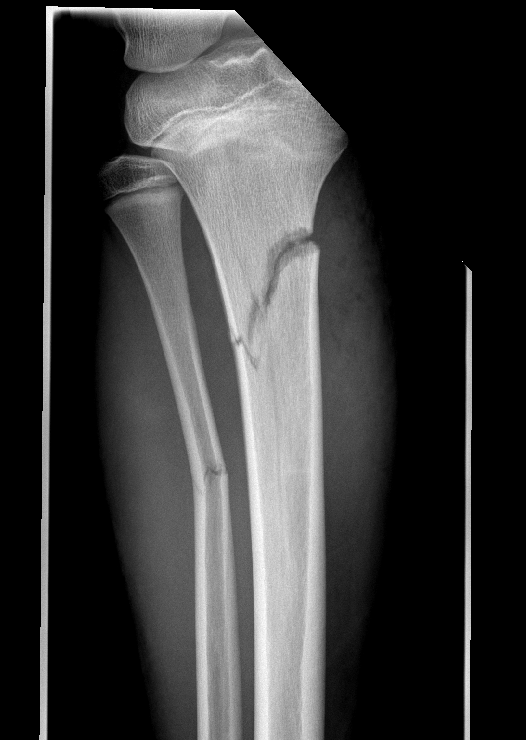

Tell me you’re an ortho resident without actually telling me you’re an ortho resident. #orthotwitter